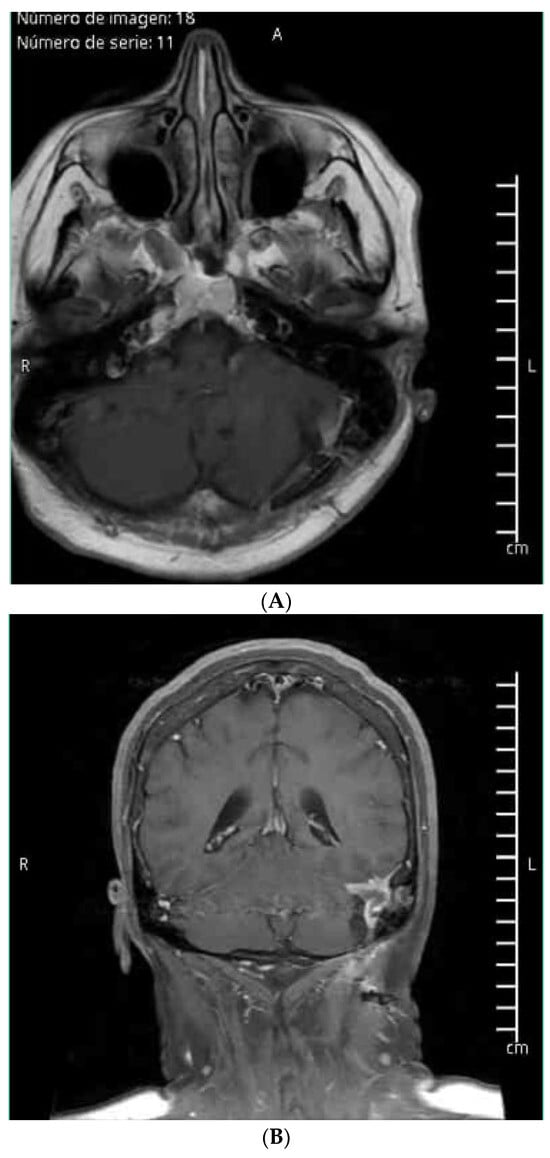

- Case 3: The use of AR in guiding craniectomy for a pre-rolandic lesion ensured complete resection with excellent functional recovery, demonstrating the precision and effectiveness of AR in locate cortical tumor and the main benefit was knowing the exact topographic relationship of vascular structures where we performed a classic craniotomy and posterior interhemispheric dissection preventing the risk of an inadvertent vascular lesion.